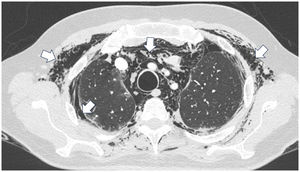

Case presentationCase 1A 60-year-old woman with a history of DM with positive anti-MDA5 antibodies diagnosed one year ago presented at the time of diagnosis with skin involvement of heliotrope rash, shawl sign, Gottron's sign, and violaceous and ulcerated lesions on the palms, polyarthritis, proximal muscle weakness of all 4 limbs, and cephaloparesis. At baseline, she was prescribed methotrexate 20 mg weekly and prednisolone 20 mg daily in a tapering regimen. After 3 months of follow-up, her skin lesions, muscle weakness, and marked elevation of muscle enzymes persisted, and she also had alopecia, a potential adverse effect of methotrexate was therefore considered, in addition to clinical refractoriness, and we decided to start the first cycle of rituximab 1 g IV on days 0 and 15, plus azathioprine 100 mg daily. She consulted after 2 months due to persistence of skin lesions and polyarthritis, despite improvement in muscle weakness and normalisation of muscle enzymes. Physical examination revealed swelling of the proximal interphalangeal, metacarpophalangeal, carpal and elbow joints, with additional heliotrope rash, Gottron papules, macules, and erythematous-violaceous plaques with incipient signs of ulceration (Fig. 1). There were also crypts in both lung fields, and therefore a high-resolution CT scan was requested, which showed isolated extensive pneumomediastinum without the presence of pneumothorax or cutaneous emphysema (Fig. 2). Oesophageal perforation was ruled out by upper gastrointestinal endoscopy and bronchial lesion by bronchoscopy; therefore, this finding was attributed to a manifestation of DM, in the absence of ILD. Given the clinical stability and the absence of respiratory symptoms, cyclophosphamide 500 mg IV monthly for 6 months was started. She is currently being monitored by the outpatient clinic awaiting completion of the proposed regimen, with clinical improvement of the skin lesions and dyspnoea.